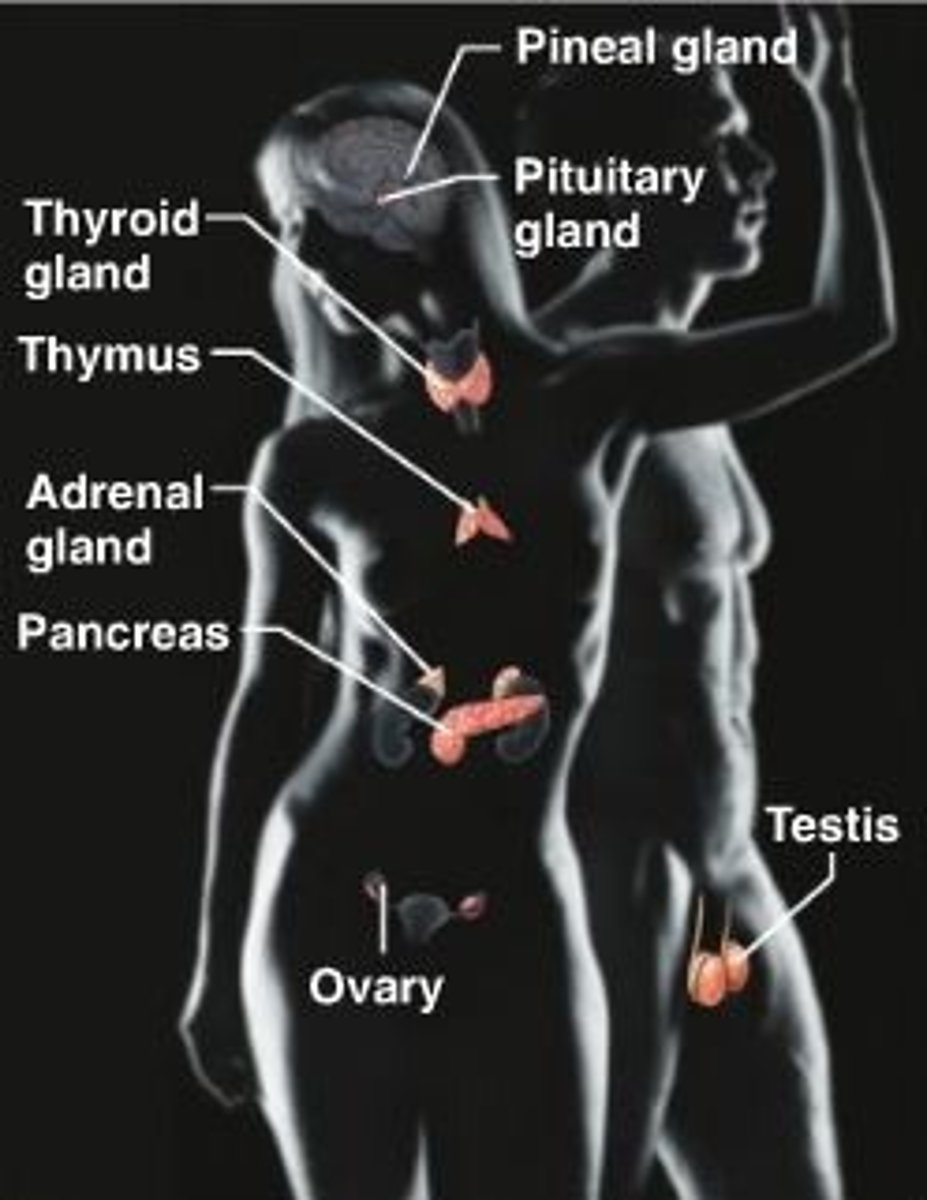

Testes

male gonads

Ovaries

female gonads

hypothalumus

small area near the base of the brain that is above the pituitary gland

pituitary gland

gland at the base of the brain that dangles under the hypothalamus

Pineal Gland

small pea sized gland that can be found posterior to the thalamus

thyroid gland

endocrine gland that surrounds the trachea in the neck

Parathyroid

in the neck next to thyroid gland

Pancreas

An organs in the abdominal cavity that is deep to the stomach

Adrenal Glands

a pair of endocrine glands that sit just above the kidneys

endocrine system

the body's "slow" chemical communication system; a set of glands that secrete hormones into the bloodstream